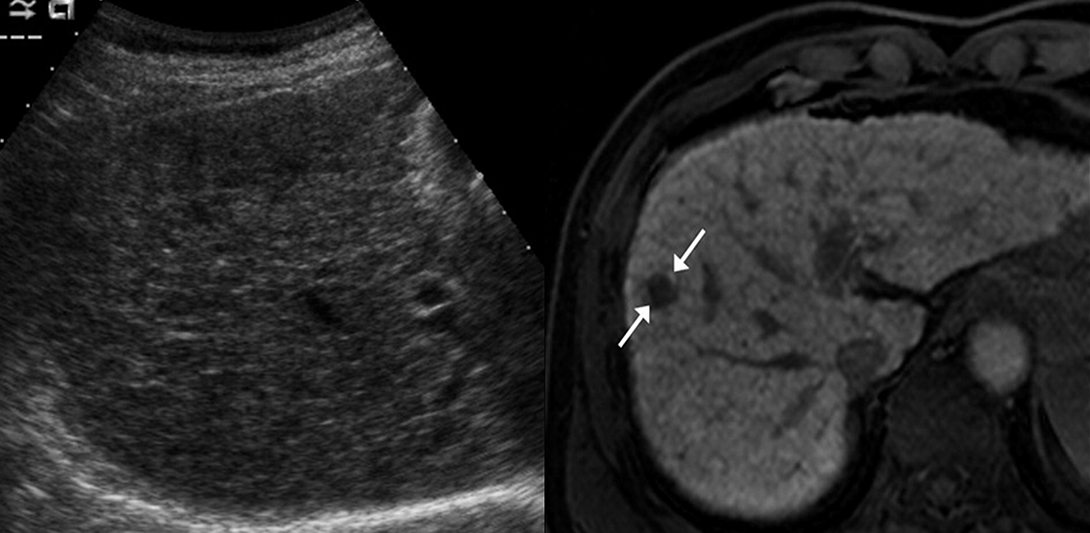

In conventional US guidance, some liver tumours have low conspicuity or are nearly undetectable when imaging small lesions or tumours located in challenging regions, such as the liver dome (see Figure 9). In addition, tumour mimics, such as regenerative nodules and prior ablation sites, may cause further confusion, making it even more challenging for physicians to accurately identify the tumour, as shown in Figure 10.

Invisible tumour 1

Figure 9. Left: invisible tumour in US; Right: visible tumour in MRI

Invisible tumour 2

Figure 10. Left: benign regenerative nodule; Right: malignant HCC